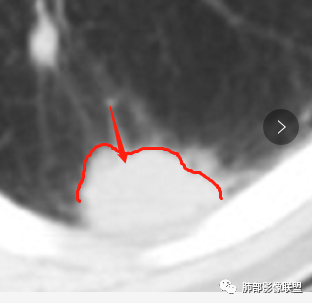

南边:糊墙,长轴与胸膜平行;边缘收缩+膨隆;脐凹征

常规:隐球菌与癌鉴别

脐凹征,高度提示恶性

南边老师论述:    分叶凹陷的地方有血管,支气管进去,这个价值很大,后来引申到血管、支气管从凹陷的地方进去就叫脐凹征,就像番茄柄🍅,辣椒柄、苹果柄🍎一样的。后来就把这个做为脐凹征,95%以上的特异性。如下例:

后来发现胸膜牵拉,由远端凹陷的地方进去,他的价值也很大,诊断腺癌,几乎很少失误,后来把这个也纳入到脐凹征里。由凹陷处进入的胸膜牵拉征,由凹陷处进去的血管,都属于脐凹征。原理是由凹陷处进去的血管,因为肿瘤膨胀生长,生长过程中遇到血管,支气管区域受阻,边缘代偿性生长,膨胀的更厉害了,所以局部凹陷,前提是血管、支气管肯定在肺门侧,不会在远端有一条血管阻碍他的,可能性太小了。

脐凹征,支气管、血管引起的在肺门侧,因肿瘤生长在近端膨胀受阻的,病灶本身围绕支气管、血管周围包绕的不算,只有进去其中受阻的才算。